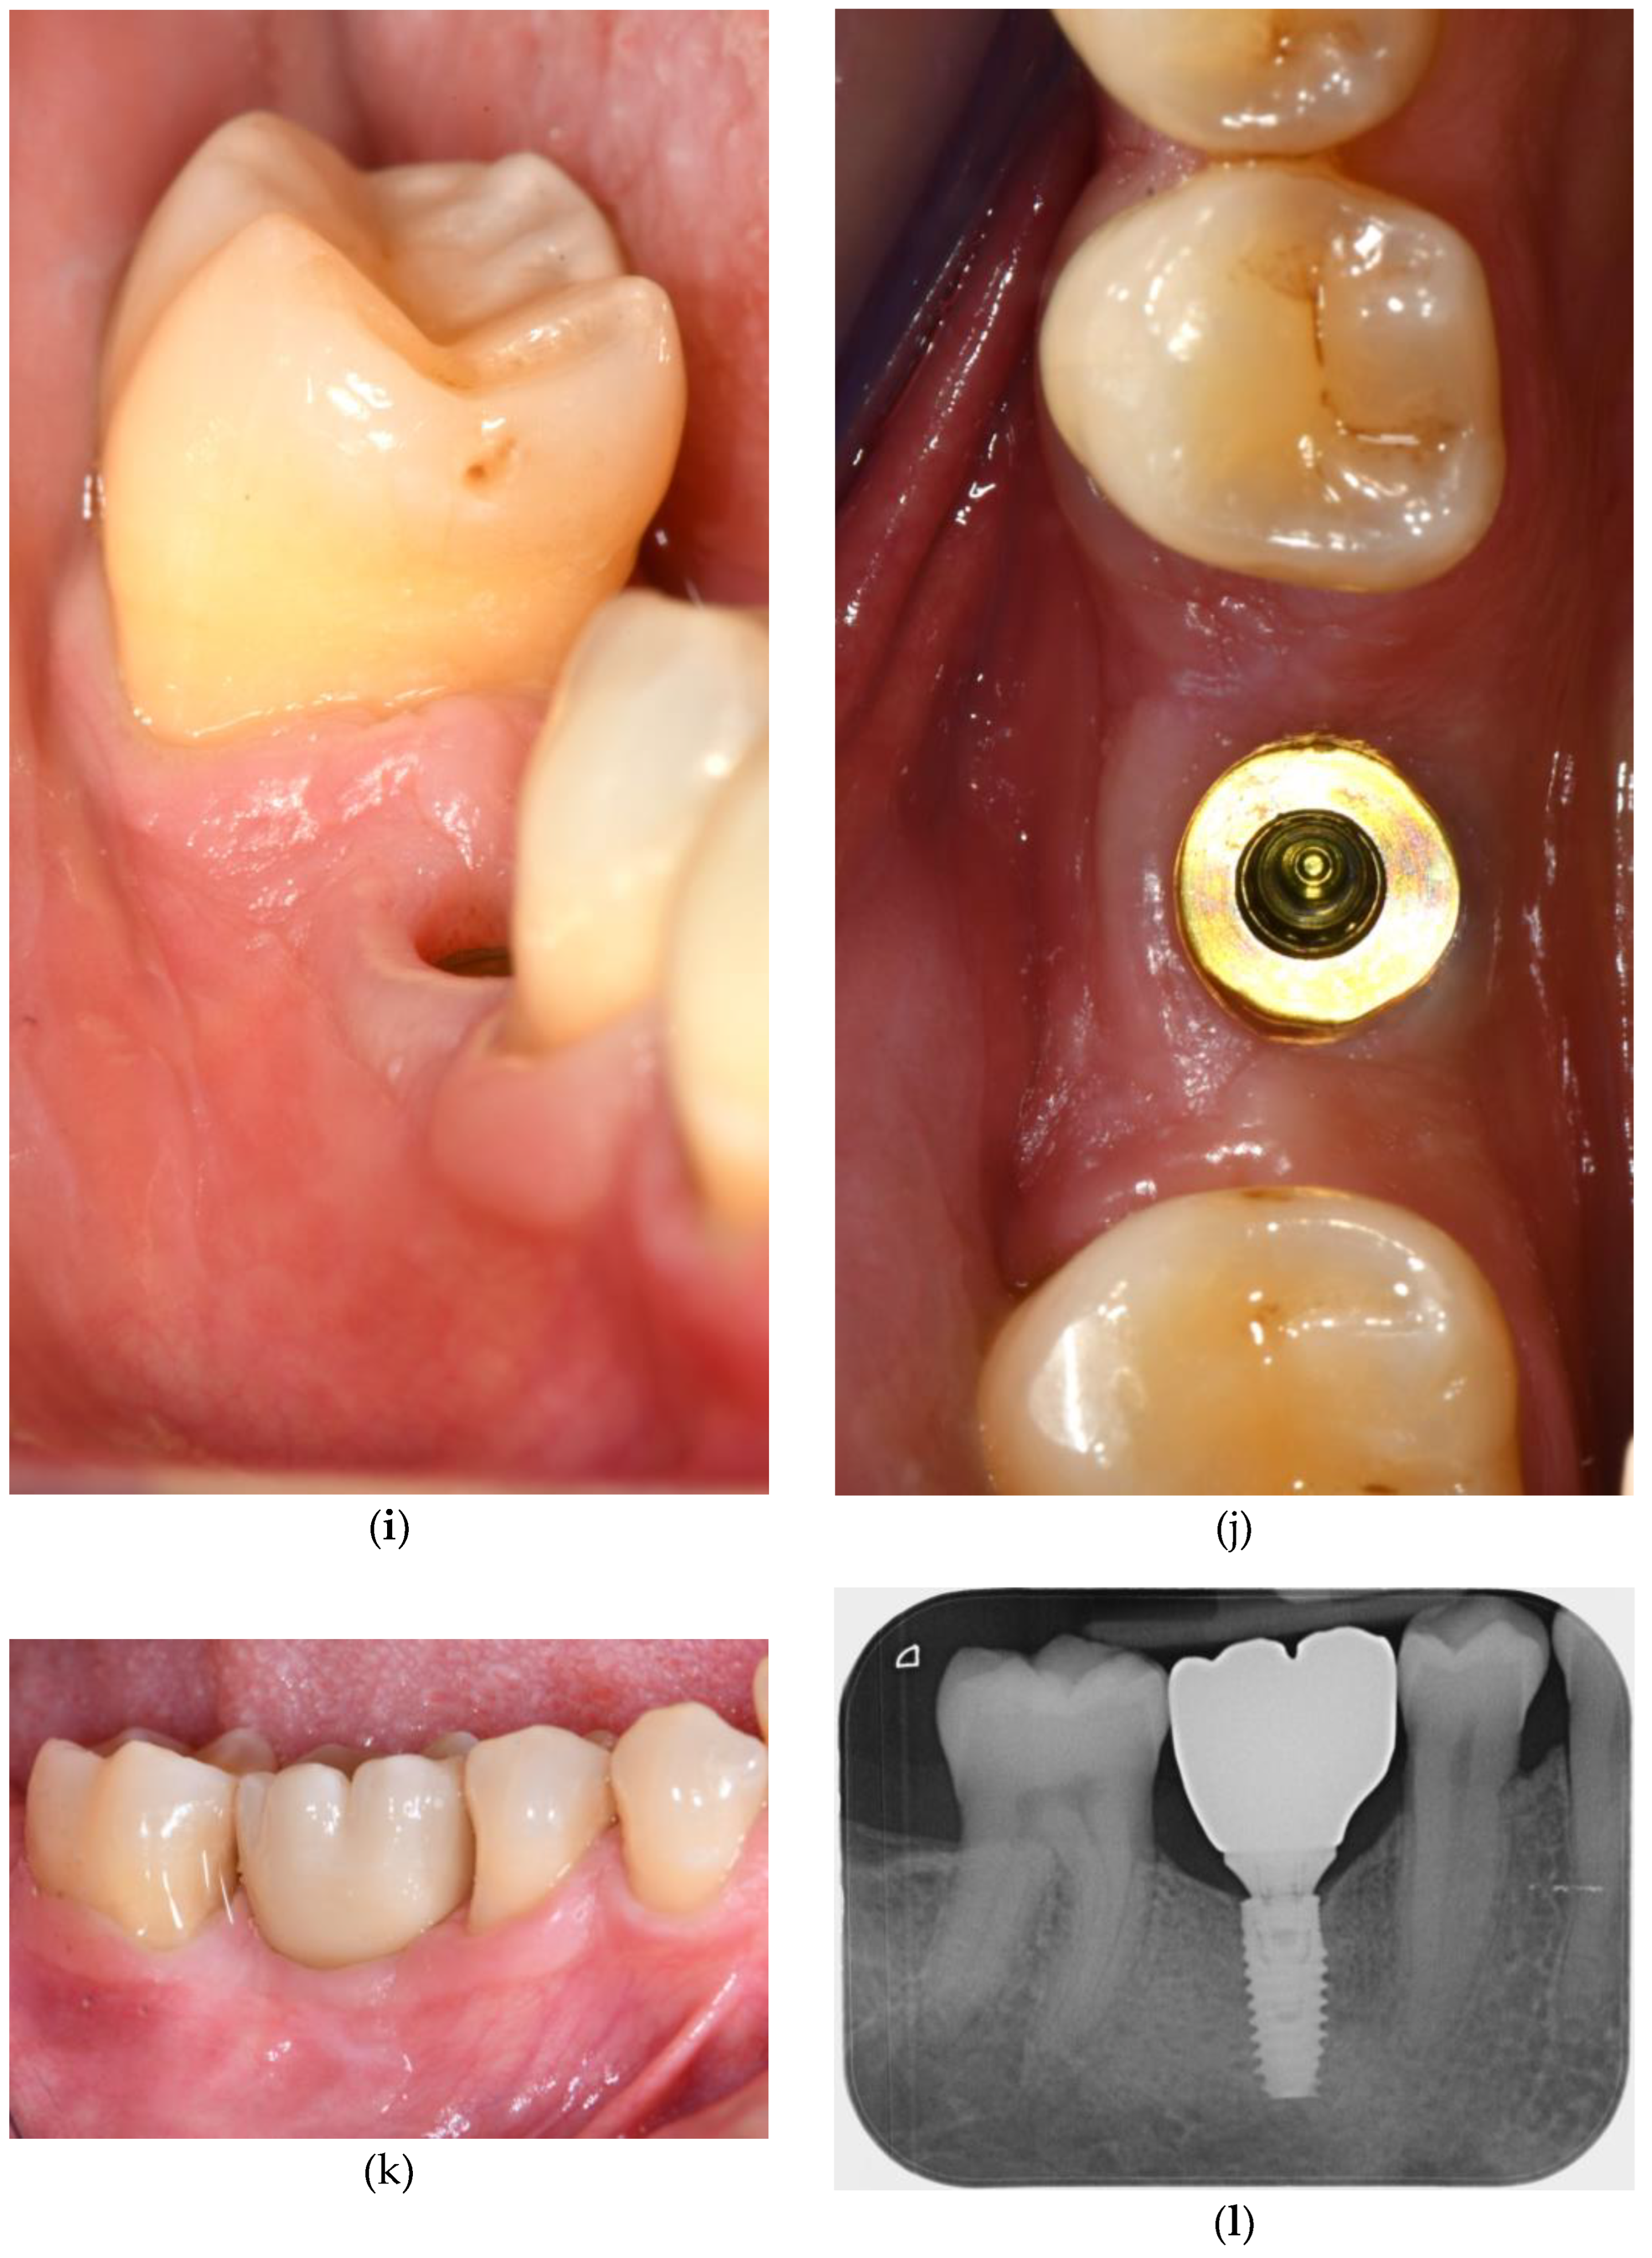

2. Connective Tissue Substitutes: Properties and Applications

3.1. Soft Tissue Augmentation Before Implant Installation

3.2. Soft Tissue Augmentation During Implant Installation

3.3. Soft Tissue Augmentation After Implant Installation